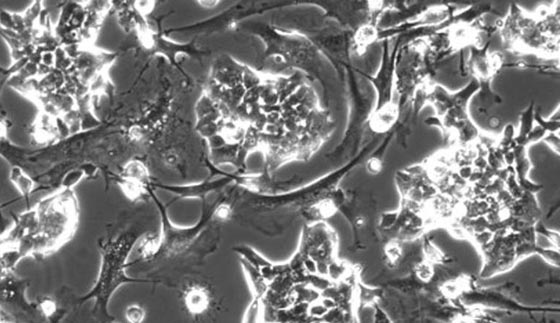

خلايا جذعية محفزة من صنع الإنسان مستخرجة من جلد وشعر بشري تنمى داخل طبق بتري